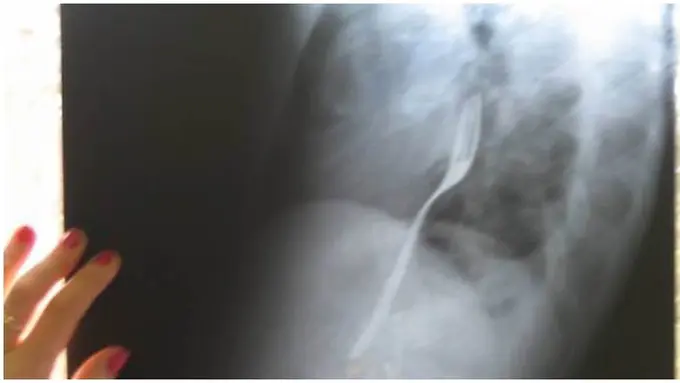

Gambar di atas adalah gambar foto rontgen dari Radu Calincescu yang bergegas ke doktor karena merasakan sakit pada esofagusnya. Pada awalnya dia hanya mengeluhkan rasa tidak nyaman pada leher dan tidak menyebutkan penyebabnya pada dokter.

Dokter pun melakukan pengecekan dengan X-Ray. Betapa terkejutnya dia setelah menemukan benda asing dari logam yang berbentuk memanjang di kerongkongan Radu. Akhirnya pria berusia 25 tahun ini mengaku jika dia telah menelan sebuah garpu.

Dilansir metro.co.uk, kejadian ini bermula saat Radu dan temannya pergi untuk minum-minum. Dia berkata pada temannya bahwa dia dapat menelan garpu tanpa merasa sakit. "Saat aku minum dengan temanku, aku bertaruh dengannya bahwa aku dapat menelan sebuah garpu tanpa terluka," ungkap Radu.

Radu akhirnya dipulangkan ke rumahnya tanpa menjalani operasi setelah dokter berkata padanya untuk menunggu apakah garpu itu dapat keluar dengan sendirinya.

Pria ini akhirnya menunggu sampai ada pergerakan pada garpu yang di telannya. Jika garpu bergerak ke arah perut dan beresiko melukai perutnya, dia akan menjalani operasi.